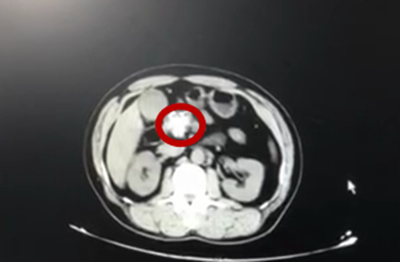

谢开汉仔细查看了吴刚的CT影像结果,发现其体内的胰管结石约有3.2CM大小,呈珊瑚状,属多发结石。谢开汉解释,当前患者的胰腺比正常胰腺萎缩明显,胰腺的内分泌和外分泌功能均受到损伤。内分泌功能主要是指胰腺调节血糖的功能受损,后期患者很可能会患上二型糖尿病,需要依靠胰岛素来调节血糖;外分泌功能主要是指后期患者的胰腺很难分泌胰酶,会影响食物的消化和吸收。